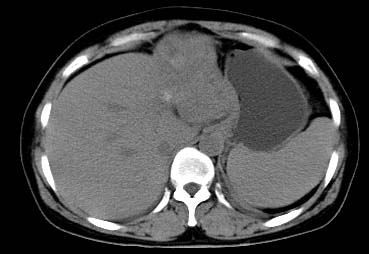

以下是引用西北一只狼在2008-6-30 20:58:00的发言:[br]肝左叶胆管细胞ca并肝门淋巴结转移、胰腺、胃小弯浸润

以下是引用ydx_74在2008-6-30 21:54:00的发言:[br]左叶胆管细胞ca并肝门淋巴结转移、胰腺、胃小弯浸润